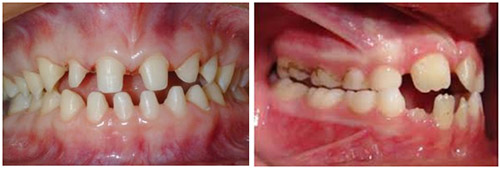

Ангидротическая эктодермальная дисплазия (синоним — синдром Криста-Сименса-Турена)

Эктодермальная дисплазия проявляется практически сразу после рождения и сопровождает человека на протяжении всей жизни. Это заболевание в основном затрагивает мальчиков, в то время как девочки (гетерозиготные) могут испытывать изменения в зубах, такие как микро- и гиподонтия (недостаточно развитые или отсутствующие зубы).

В ротовой полости заболевание проявляется аномалиями зубов, такими как гиподонтия, микродонтия и анодонтия. Зубы появляются значительно позже обычного, долго остаются в стадии молочных, могут отсутствовать частично или полностью, часто с большими промежутками между ними, и имеют значительные деформации.

Кожа вокруг рта может образовывать складки из-за деформации зубов. Старческий вид лица возникает из-за уменьшения нижней трети лица при полном отсутствии зубов и выраженной супраментальной складки.